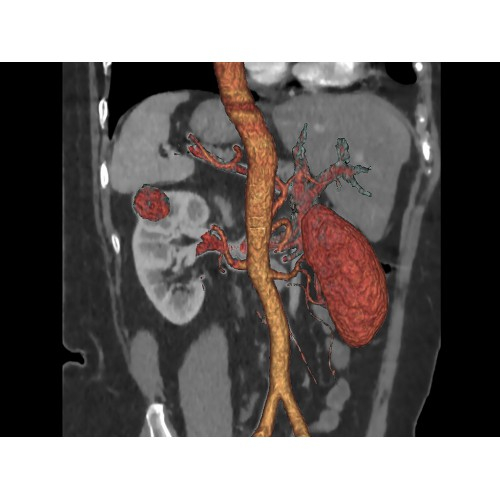

• Широкая область применения: от неврологии до кардиологии и онкологии.

КТ аппарат GE Optima CT520 используется для диагностики широкого спектра заболеваний:

• Неинвазивная оценка состояния коронарных артерий.

• Диагностика атеросклероза и других сердечно-сосудистых патологий.

Онкология

• Раннее выявление новообразований и контроль эффективности лечения.